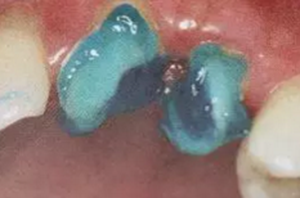

使用全酸蝕粘接系統(tǒng)粘接纖維樁時(shí),用磷酸凝膠對(duì)根管進(jìn)行酸蝕處理,然后再徹底沖洗干凈,根管內(nèi)酸蝕劑殘留的發(fā)生容易被忽視,這也是影響纖維樁粘接的重要因素之一。

單純的使用三用槍即使反復(fù)沖洗液難將根管內(nèi)的酸蝕劑沖洗盡,尤其是后牙根管。

(冠部及根管全酸蝕)

(三用槍沖洗)

(注射器沖洗)

(根管毛刷清洗)

臨床建議用注射器、三用槍和柱狀毛刷,三者聯(lián)合反復(fù)沖洗。如再配合超聲波振蕩沖洗更佳。